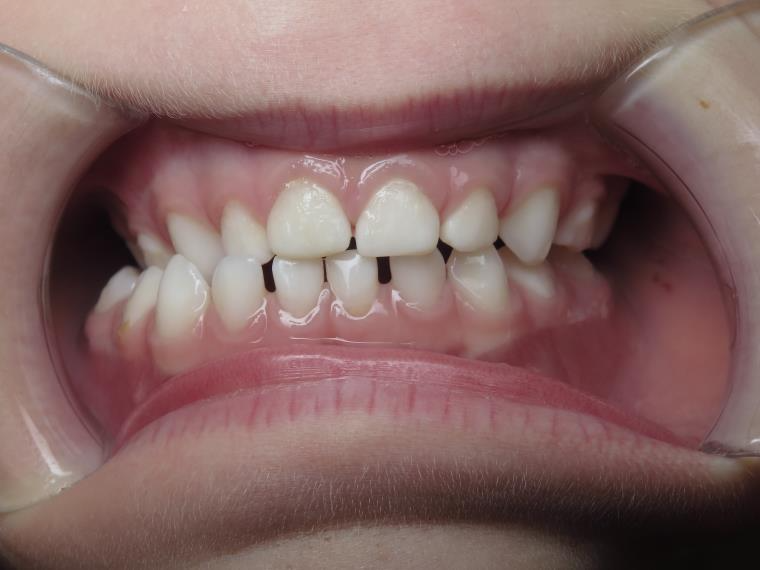

bilan début et en cours de traitement